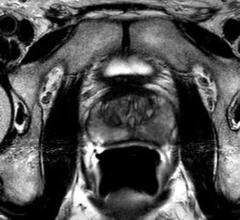

Researchers at the University of Michigan have developed the first-ever 3-D complete computer model to help study treatment for pelvic organ prolapse, a mysterious condition often linked to childbirth.